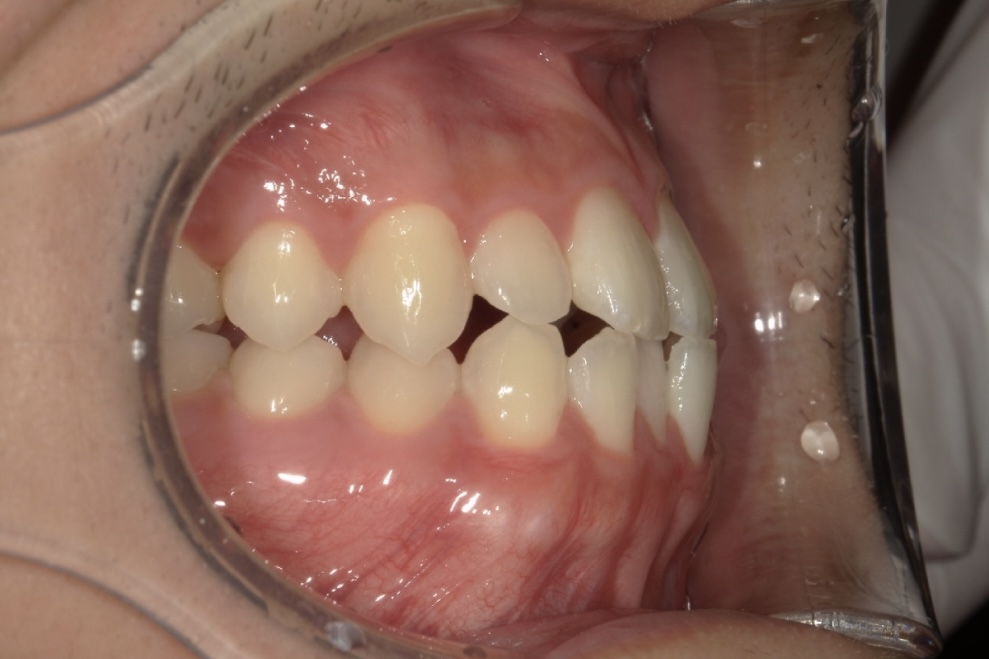

Before 1

Before 2